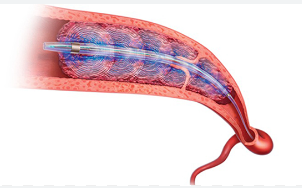

导管的远端有一个可膨胀的球囊,膨胀后可以暂时阻断血流,防止血栓碎片流向远端。

导管尖端部分有多个(通常是三个)可展开的镍钛合金网篮。这些穿过血栓,将其“搅碎”并捕获。

抽吸与清除:在网篮捕获血栓的同时,导管连接一个大型的专用抽吸 syringe(注射器),提供强大的手动抽吸力,将碎裂的血栓吸出体外。

重复操作:医生会多次移动、展开、抽吸,直到清除大部分血栓,恢复肺动脉的血流。